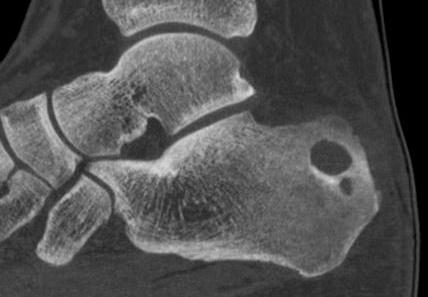

Talus

1. Head and neck

- medial approach between Tibialis anterior and Tibialis posterior

2. Body

- lateral Ollier's approach between Peroneus tertius and Peroneus brevis

Calcaneum

Direct lateral approach